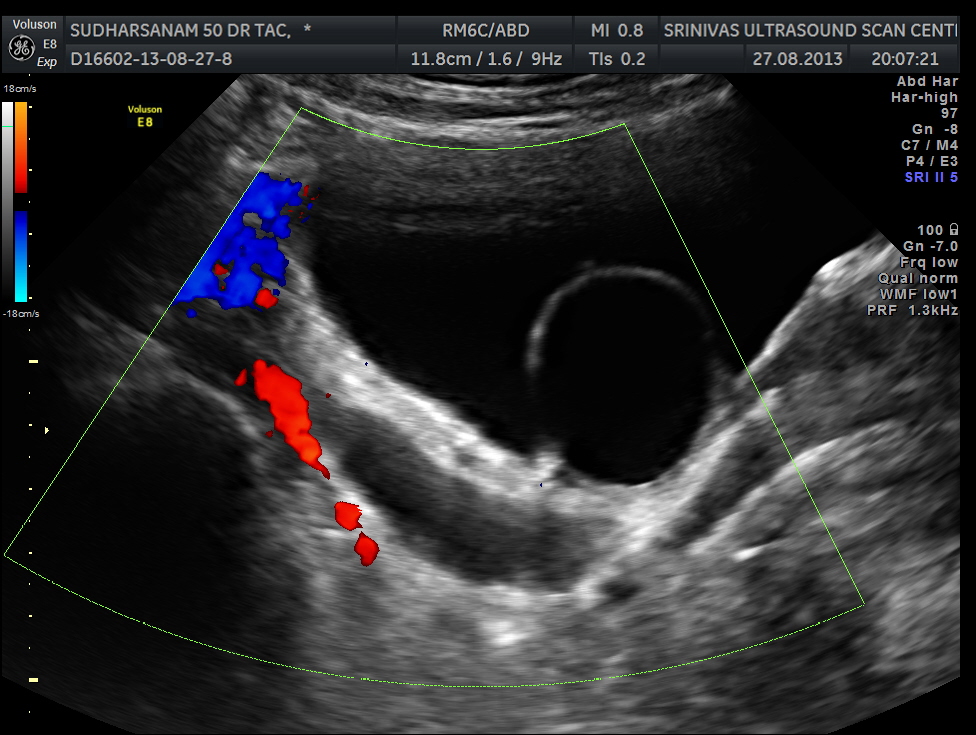

given below are few other reconstructions

The patient was seen by the urologist and an IVP was done , which proved the diagnosis of orthotopic ureterocele . (a ureterocele entirely within the bladder.)